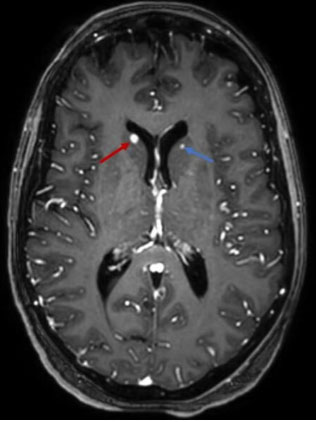

Brain MRI showed multiple nodular lesions in the frontal, parietal, occipital, and temporal lobes, in addition to the cerebellar hemispheres, not exceeding 2 cm in size, hyperintense on T1, hypointense on T2 and T2*, with nodular and ring-like enhancement after contrast (Figure 3, Figure 4, Figure 5), suggesting a melanomatous origin, in favor of a cerebral relapse of the anorectal melanoma.

Figure 5: An axial T1 post-contrast MRI image showing a ring-like enhancing lesion in the right caudate nucleus (red arrow) and a homogeneously enhanced nodular lesion in the left caudate nucleus (blue arrow).

Post-contrast T1 WI: It is the Gold standard for the diagnosis of cerebral metastases. It demonstrates nodular or ring-like enhancement [8],[10].